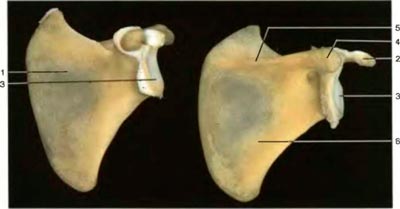

Окостенение лопатки (слева: вид спереди, справа: вид сзади) |

1. Подлопаточная ямка

2. Клювовидный отросток

3. Суставная впадина

4. Плечевой отросток

5. Ость лопатки

6. Подостная ямка

1. Fossa subscapularis

2. Processus coracoideus

3. Cavitas glenoidalis

4. Acromion

5. Spina scapulae

6. Fossa infraspinata |